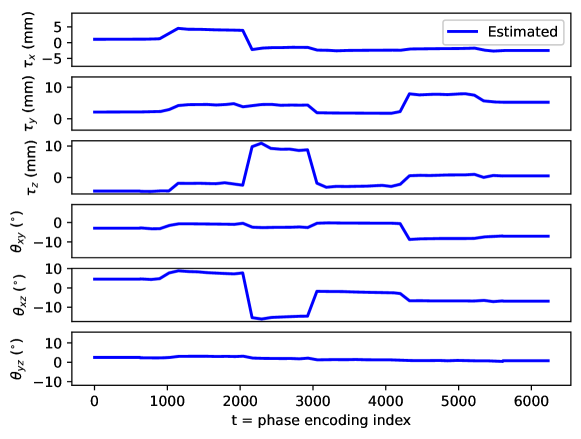

Appendix C Motion parameter estimation

The proposed motion correction algorithm described in Section 2 estimates the rigid motion that the object of interest undergoes during the scan, in order to undo its effect on the reconstructed 3D image. In 3D, the rigid motion is performed by: a plane rotation in the corresponding plane , a plane rotation in the plane, a plane rotation in the plane, a translation in the direction, a translation in the direction, and a translation in the direction (in this order). We adopt the following convention: the direction corresponds to the left-right direction, to the posterior-anterior direction, and to the inferior-superior direction, the plane corresponds to the axial plane, to the coronal plane, and to the sagittal plane. Left/right, anterior/posterior, and inferior/superior are meant from the patient perspective. The orientation of the rotation planes is determined by the right-hand rule.

By design, the prospectively-induced motion for all the experiments detailed in Section 3 follows a step-wise behavior (each step corresponding to a change of pose). In this appendix, we gather the estimated rigid motion parameters for the results shown in Section 4, as a function of time. As noted in the main body of the paper, time is equated to the phase-encoding plane coordinate index, ordered by the corresponding acquisition ordering. We display the estimated motion parameters in Figure 19 (see Sections 3.1, 4.1, Figure 2), Figure 20 (see Sections 3.1, 4.1, Figure 4), Figure 21 (see Sections 3.1, 4.1, Figure 6), Figure 22 (see Sections 3.2, 4.2, Figure 10), Figure 23 (see Sections 3.3, 4.3, Figure 12), and Figure 24 (see Sections 3.3, 4.3, Figure 14).